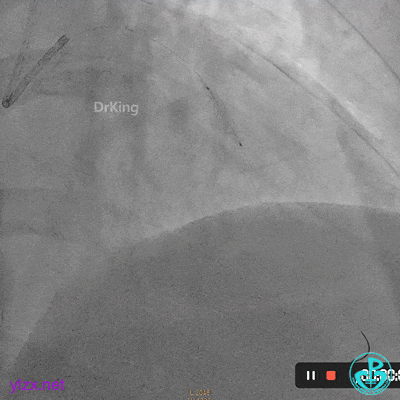

03 急诊冠脉造影

右冠脉粗大,近中段瘤样扩张明显,中段闭塞,局部可见大块血栓影。

前降支开口至近段明显瘤样扩张,中段闭塞,第一对角支粗大,无明显狭窄。

LCX发育小,内膜不光滑,血流3级。